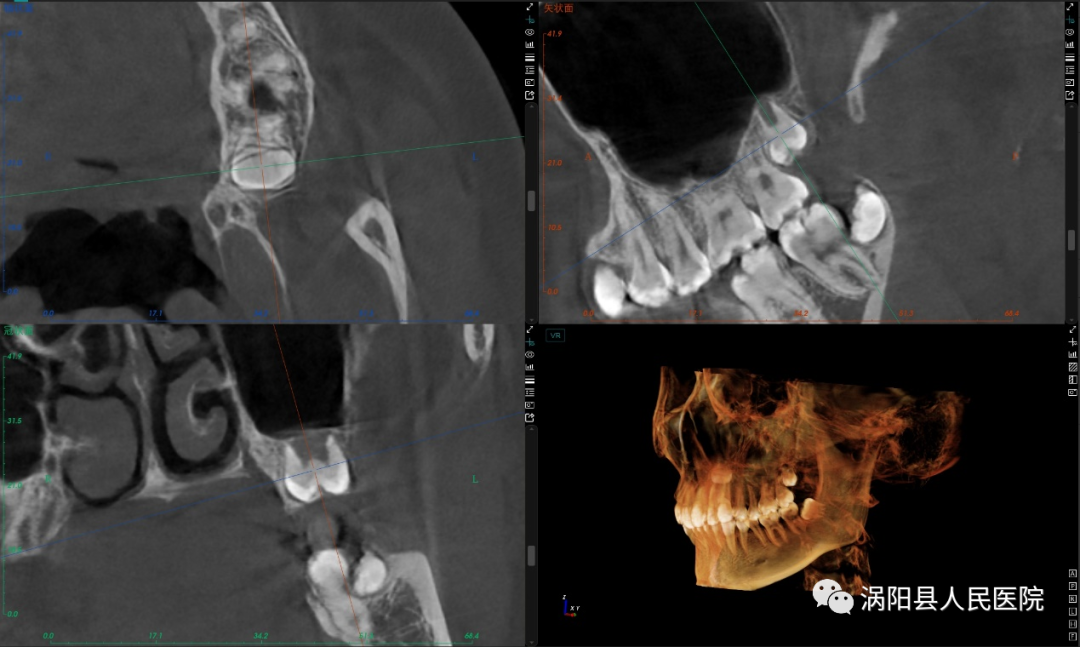

患者术前影像资料,可见上颌双侧第三磨牙埋伏阻生且位置较深、属超低位阻生,距离上颌窦较近。

拔除后的上颌双侧第三磨牙